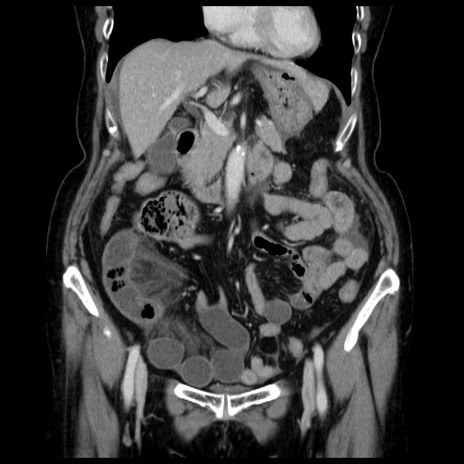

症例13(冠状断像)

【症例】70歳代女性

【主訴】腹痛、嘔吐

【現病歴】15時間程前(昨晩)より腹痛あり。今朝になっても症状の改善なく、嘔吐あり。腹痛も増悪あり、救急外来受診。

【既往歴】子宮癌全摘術後

【身体所見】意識清明、BP 121/72mmHg、P 74bpm、SpO2 100%(RA)、腹部:平坦・軟、腸雑音ほぼ聴取せず。下腹部・心窩部・臍左上に圧痛あり。反跳痛なし。

【データ】WBC 10600、CRP 0.15

横断像